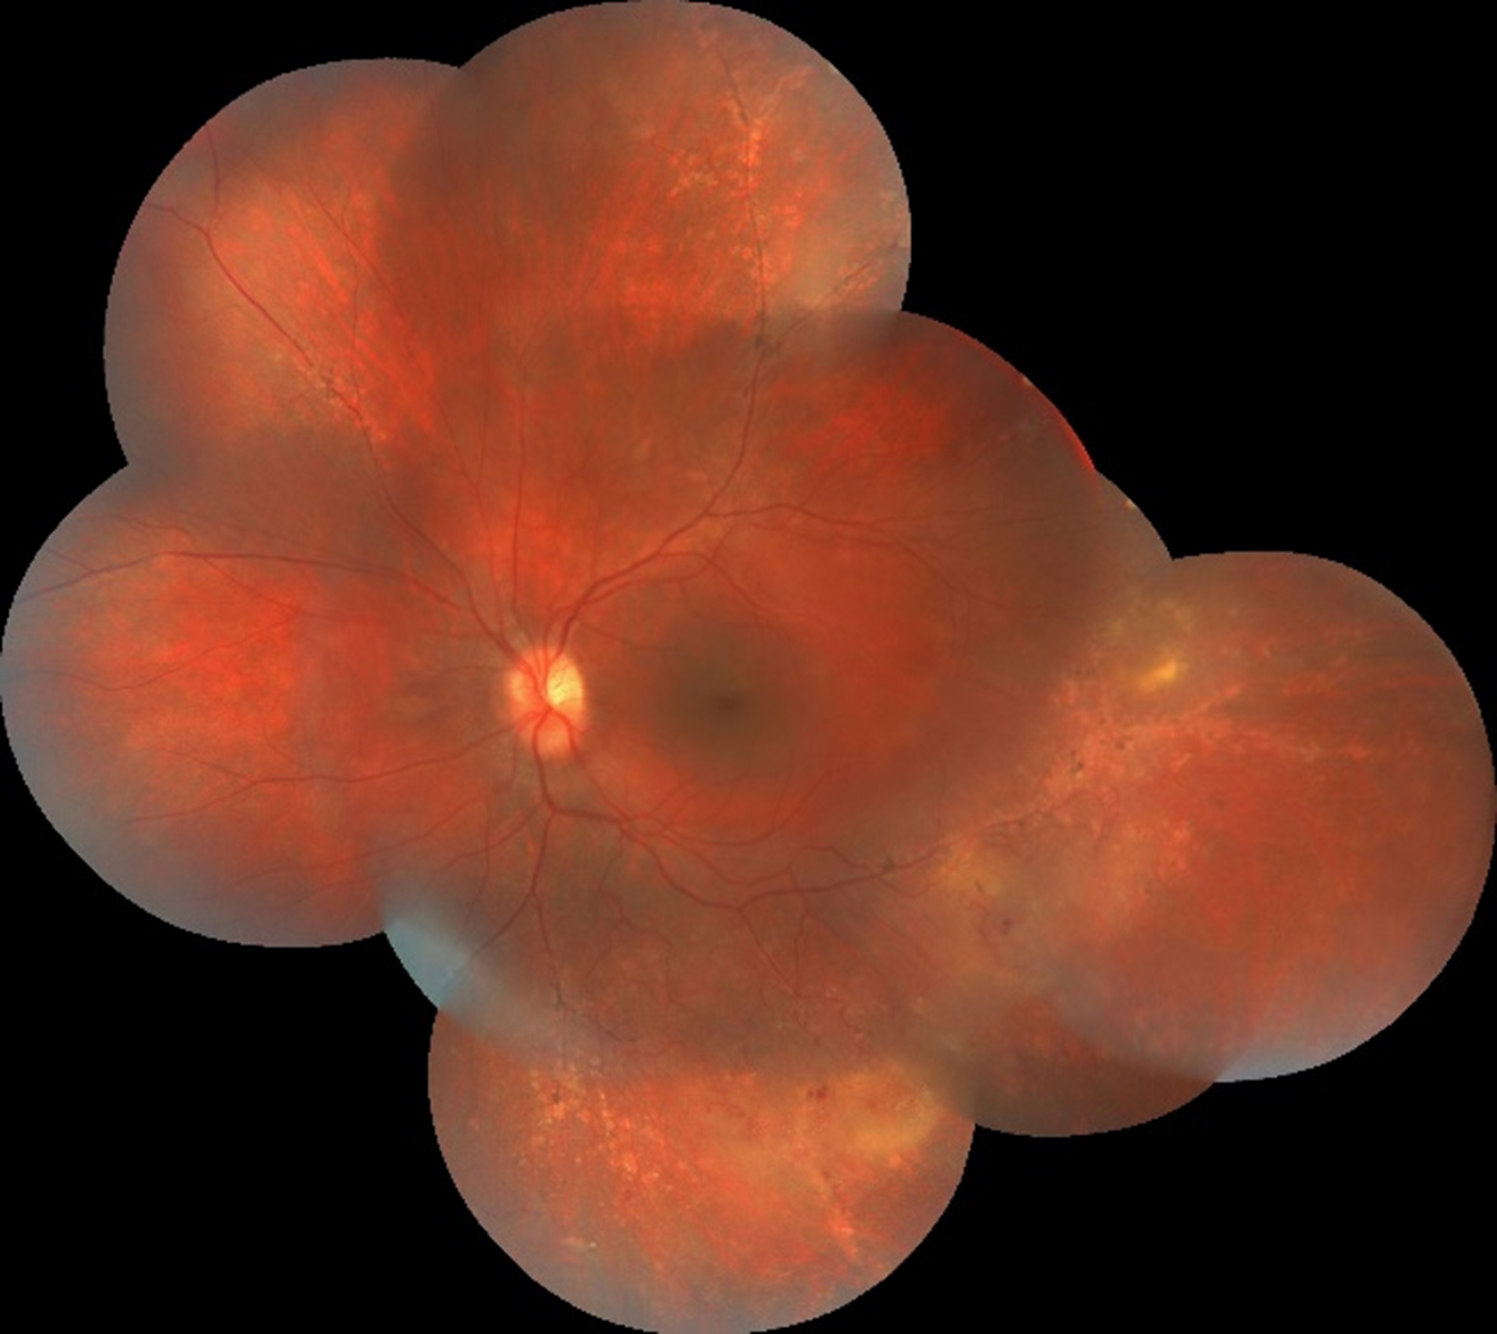

Her iki gözde doğuştan bu yana görme problemleri olan 11 yaşındaki erkek hastanın sağ gözünün görme keskinliği 0,7, sol gözünün 0,9’dur. Hastanın her iki göz renkli fundus fotoğrafını görmektesiniz. Bu görüntülere bakarak tanı ve sağ göz bulgusu için ne söyleyebilirsiniz? Lütfen cevabınızı aşağıya yazınız.